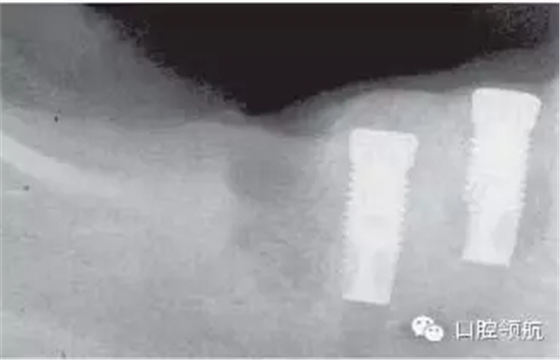

圖2.9 一位64歲的婦女,患有乳腺癌,接受化療和靜脈注射雙磷酸鹽藥物,3年后拔牙、種植。X光檢查發(fā)現(xiàn)骨壞死。